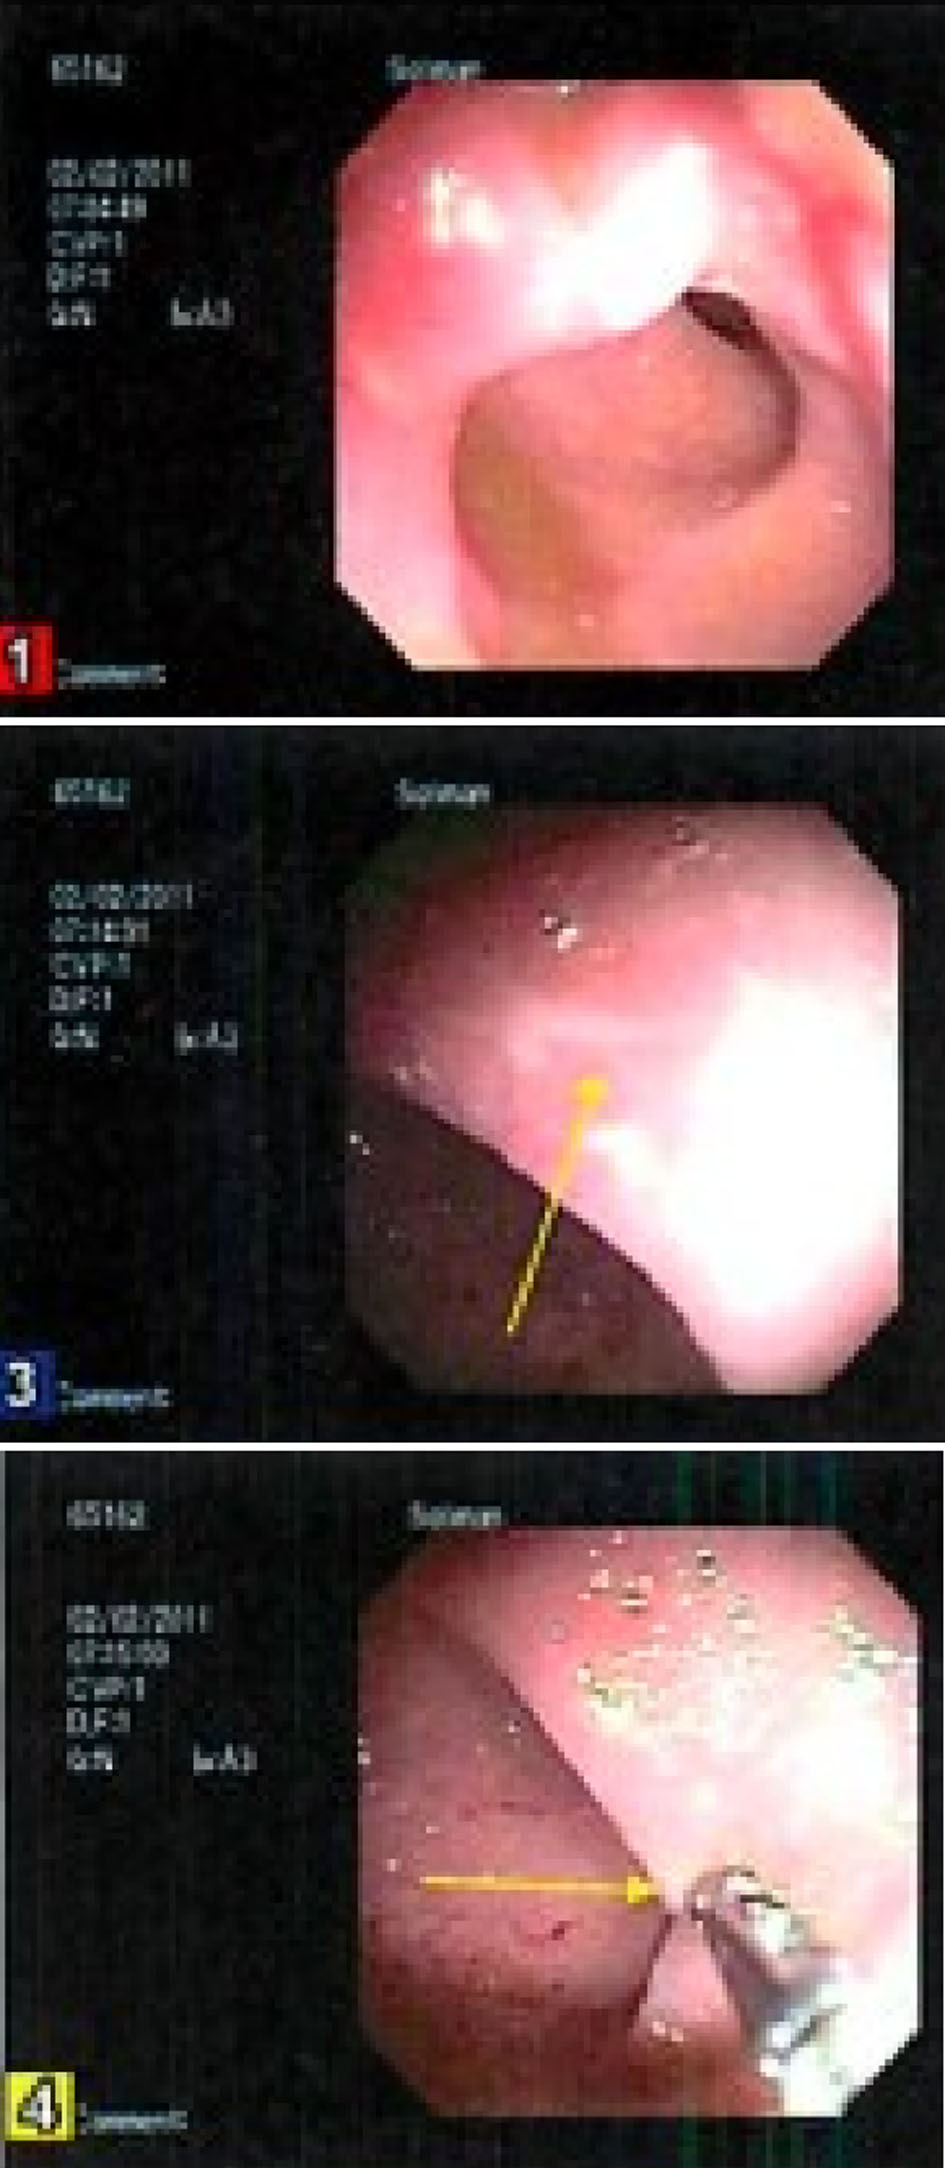

A 15-year-old male with a past medical history of chronic constipation and stool incontinence presented to the hospital with fatigue, weakness, dizziness, pallor, headache, and frequent episodes of diarrhea. He had a weight loss of 30 pounds over the last 18 months which he attributed to a very poor appetite. He denied any vomiting, rectal bleeding, hematemesis, or abdominal pain. There were no recent sick contacts. Family medical history was only positive for diabetes mellitus in his father. On physical exam, he appeared ill, thin and pale, but all other systems were negative. Rectal exam was normal without any perianal lesions or frank blood. Neurologic exam showed that he was alert and oriented, with cranial nerves II to XII intact, no unilateral weakness, and good tone and strength throughout. At the time of admission, he was afebrile with a heart rate of 124 beats per minute, blood pressure of 126/64 mm Hg, respiratory rate of 20, and oxygen saturation of 99%. On his CBC, he was found to have hemoglobin 6.6 g/dL requiring two iron transfusions. Labs showed normal calprotectin, anti-gliadin IgA and IgG levels, and negative stool cultures for Clostridium difficile, Campylobacter, Salmonella, Vibrio, and Yersinia. CRP was slightly elevated at 2 mg/L and ESR was elevated at 48 mm/h (Table 1). An abdominal ultrasound showed some biliary sludge with no other abnormal findings. Colonoscopy only showed rectal edema, no obvious ulcerations, with some exudate (Fig. 3). However, the pathology report showed a severely active chronic colitis with ulcerative mucosa with numerous neutrophils and granulation tissue formation in his rectum. Magnetic resonance enterography (MRE) showed bowel inflammation and wall thickening of the rectum as well as fibrofatty plaque formation and edema around the rectum. His differential diagnoses included IBD, short segment Hirschsprung’s disease, and non-infective gastroenteritis and colitis. He was started on oral ferrous sulfate 325 mg BID and instructed to follow-up in 1 week.

![]() Click for large image | Figure 3. Colonoscopy results during hospital admission showing a localized area of moderately congested mucosa and exudate found in the rectum. |

At his 1-week follow-up visit, he was asymptomatic. On physical exam, he appeared pale but the rest of the exam was normal. Rectal exam showed no perianal lesions and internal rectal exam showed some dark stool that did not resemble blood. However, his hemoccult was positive, so he was started on mesalamine suppository 1 g QD until his next follow-up visit. Because of his normal inflammatory markers and normal fecal calprotectin levels during the hospital admission, treatment for IBD was held. At his 1-month follow-up visit, his hemoccult was negative and subsequent labs, endoscopy, and colonoscopy were repeated. Upper endoscopy showed an incidental finding of eosinophilic esophagitis (EOE) as well as mild chronic inflammation in the gastric antrum. Colonoscopy showed focal acute and chronic inflammation with erosions and ulcers without granulomas and dysplasia. Biopsies taken from the transverse colon, cecum, and terminal ileum were all normal. The diagnosis of SRUS was made due to his colonoscopy results and the thickening of his rectum previously seen on MRE, as well as the inflammation seen on magnetic resonance imaging (MRI) was attributed to his chronic constipation and straining. Labs showed improved hemoglobin levels at 10.3 g/dL, low iron saturation at 4%, low iron levels at 20 µg/dL, elevated total iron binding capacity at 469 µg/dL, and low serum ferritin at 7 ng/mL. A diet history obtained at this point showed a very picky eater suggesting this was the more likely cause of anemia. He was started on oral omeprazole 40 mg for EOE, and a repeat endoscopy has been planned to see if his EOE is proton pump inhibitor responsive. He was continued on mesalamine suppository 1 g QD as needed and ferrous sulfate 324 mg for his rectal ulcer and iron deficiency anemia. He was also started on oral docusate 200 mg daily to help with regular bowel movements. At his 6-month follow-up visit, he reported being clinically asymptomatic and no longer had fecal impaction. His mesalamine suppository was stopped since he had been stooling daily with the docusate. Omeprazole 40 mg was continued and his repeat endoscopy has been scheduled 2 months from now. He will also have a repeat colonoscopy at the same time to follow-up on the solitary rectal ulcer.

Further investigation of symptoms, macroscopic findings and histopathologic reports suggest SRUS as a more accurate diagnosis. IBD and malignancy are differentiated from SRUS with histopathology findings. Some microscopic abnormalities of IBD are: crypt atrophy, which includes crypt shortening and widening of spaces between crypts, increased inflammation markers, and the presence of granulomas and mucin depletion [11]. Yet, SRUS follows the characteristic appearance of fibromuscular obliteration in the lamina propria, thickening of the mucosal layer, mucus proliferation and gland distortion and mild inflammation [9]. However, there are sometimes minor microscopic changes seen in SRUS such as surface erosion, reactive hyperplasia, mild inflammation, and distorted crypts that may lead to false diagnosis of IBD [5]. In the first case, colonoscopy revealed a single rectal ulcer and histology confirmed this solitary ulcer with necrotic exudate and acute and chronic inflammatory cells with atrophic, reactive mucosal glands. In the second case, colonoscopy showed wall thickening of the rectum, focal acute and chronic inflammation with erosions and ulcers. However, in both cases, there were no granulomas or dysplasia seen in histology and inflammatory markers such as fecal calprotectin, ESR, and CRP were all normal, thus supporting the benign nature of SRUS. Additionally, in both cases, biopsies taken from the transverse colon, cecum, and terminal ileum were all normal.